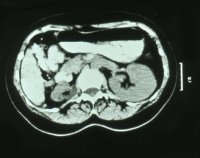

Computertomographie zur Diagnostik der kleinen Niere. Zum Beispiel eine pyelonephritisch veränderte linke Niere im Computertomogramm und im weiteren Beispiel CT und Organpräparat einer rechtsseitigen kleinen Niere.

Und in einem weiteren Beispiel CT und Organpräparat einer rechtseitigen "kleinen Niere" (Abbildung 11, 12ab).